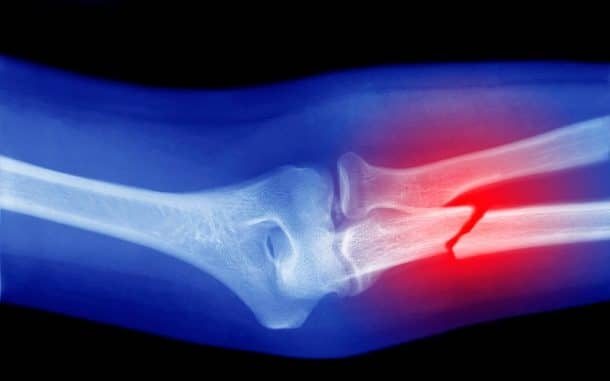

“事实上,最近x射线显示他有很多裂隙在这两个脚踝。”其他家庭成员都经历过类似的问题,与莱蒂齐亚的78岁的老母亲经历骨折,只是后来诊断意味着他们强化自然但没有痊愈。基因突变也会影响他们的能力检测极端温度,使其燃烧自己或失败的风险加大注册冰水之类的东西。